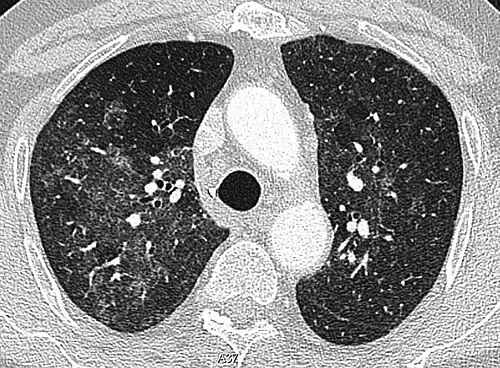

High-Resolution CT image in a patient with Pneumocystis pneumonia infection showing ground-glass opacities.